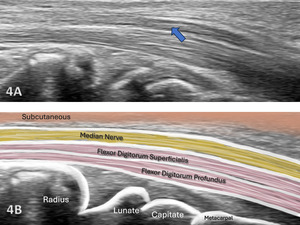

The median nerve begins as the extension of the medial and lateral cords of the brachial plexus in the axillary region. It descends in the arm lateral to the brachial artery until the insertion of the coracobrachialis, where it crosses in front, and in rare cases, behind the artery to move to the medial side of the arm near the anterior cubital fossa. At that location, it runs behind the lacertus fibrosus and is separated from the joint by the brachialis muscle. The median nerve received its name from the middle position at the end of the brachial plexus and the forearm.5 As it descends further in the forearm, it runs between the two heads of the pronator teres. From that point it runs beneath the flexor digitorum, laying on the flexor digitorum profundus more superficially as it passes underneath the transverse carpal ligament (flexor retinaculum) into the palm. At the hand, the median nerve gives motor branches to the thenar eminence, and second lumbrical muscles, as well as sensory branches to the radial half of the palm and the radial three and half digits.6 Its motor function is to the flexor aspect of the forearm, hand, and thumb to innervate the pronator teres, palmaris longus, flexor digitorum superficialis, flexor carpi radialis, and via the anterior interosseus nerve (AIN), the flexor pollicis longus, the flexor digitorum profundus, and the pronator quadratus.

The median nerve is clearly identifiable in SAX by a well circumscribed ovoid structure with hypoechoic fascicles in a honeycomb-like pattern deep to the roof of the carpal tunnel, the flexor retinaculum, and more superficial to the flexor digitorum superficialis and flexor digitorum profundus tendons. The median nerve is also very compressible and will alter its shape depending on the volume of the anatomical spaces with which it courses. The median nerve cross-sectional area (CSA) can be measured in four sites: 1) the proximal border of the pronator quadratus muscle, 2) proximal to the carpal tunnel inlet, 3) at the tunnel inlet, and 4) at the tunnel outlet.9